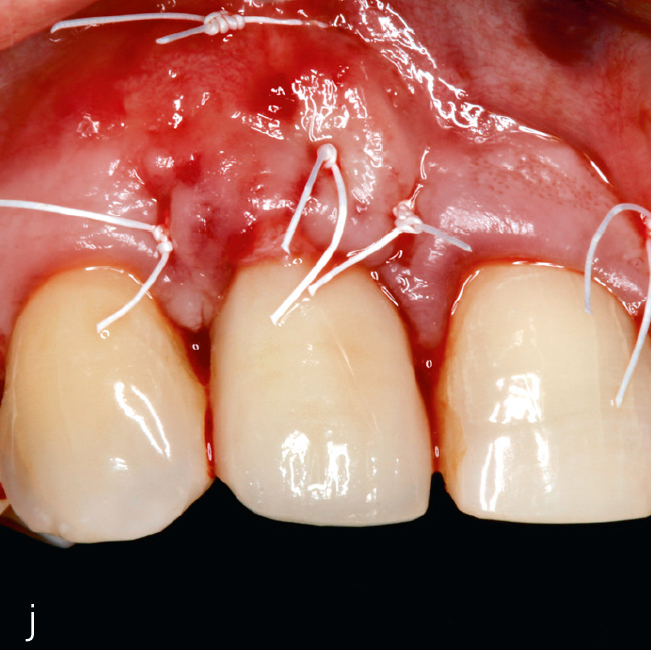

Abb. 3i bis m Falldokumentation mit Zustand nach Implantation und lateraler Augmentation alio loco: i) okklusale Ansicht mit eingebrachtem BGT vestibulär in der Region 12; j) Wundverschluss mit Naht; k) klinische Situation 9 Monate post operativ; l) okklusale Ansicht; m) klinische Parameter.